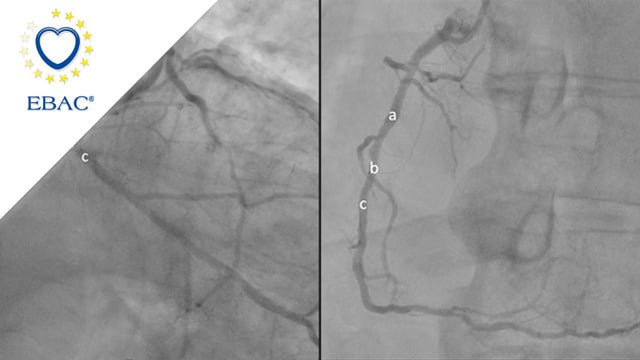

How should I treat a left main disease with multivessel diffuse CAD? Stenting only the necessary...

A 71-year-old male patient with a clinicial history of hypertension, dyslipidemia and active smoking was admitted for NSTEMI.

Coronary angiography showed a left main (LM) stenosis involving the bifurcation and proximal parts of the left anterior descending (LAD) and left circumflex (LCx) arteries. Right coronary artery (RCA) showed a severe...